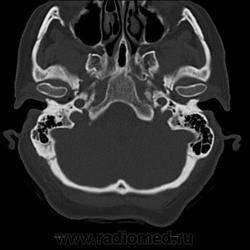

А можете показать перелом стрелкой на аксиальных сканах?

Да. Только это не аксиалы, а выровненные и несколько скошенные реконструкции для лучшего отображения линии перелома.

Известно место удара, есть линия перелома на своде. А воздух в черепе и шее заставил поковыряться